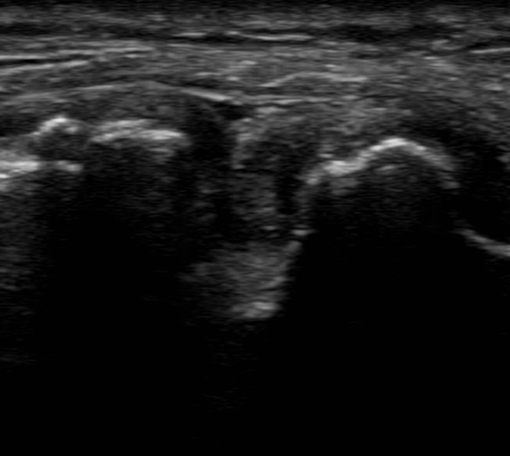

膝痛への超音波エコーガイド下鍼

膝周囲の筋肉・靱帯・神経の状態を確認しながら施術。原因を見極め、歩行時の痛みや違和感を改善へ導きます。